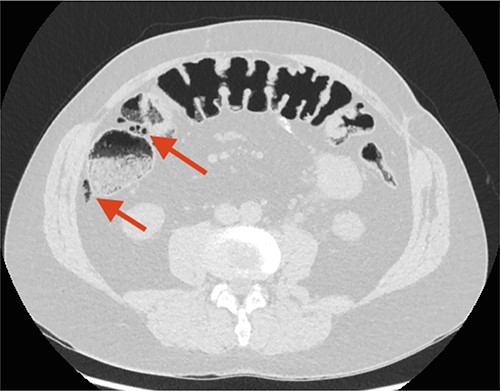

A non-contrast CT scan showed FIA located along the right colon flexure, calyceal calculi located in the left kidney and sequelae from former sigmoid colectomy with stoma formation (Fig. 1). There where no wall thickness of the colon indicating activity in the patient's Crohn's disease.

The initial CT scan. The arrow points at free intraperitoneal air (FIA) located along the right colon flexure.